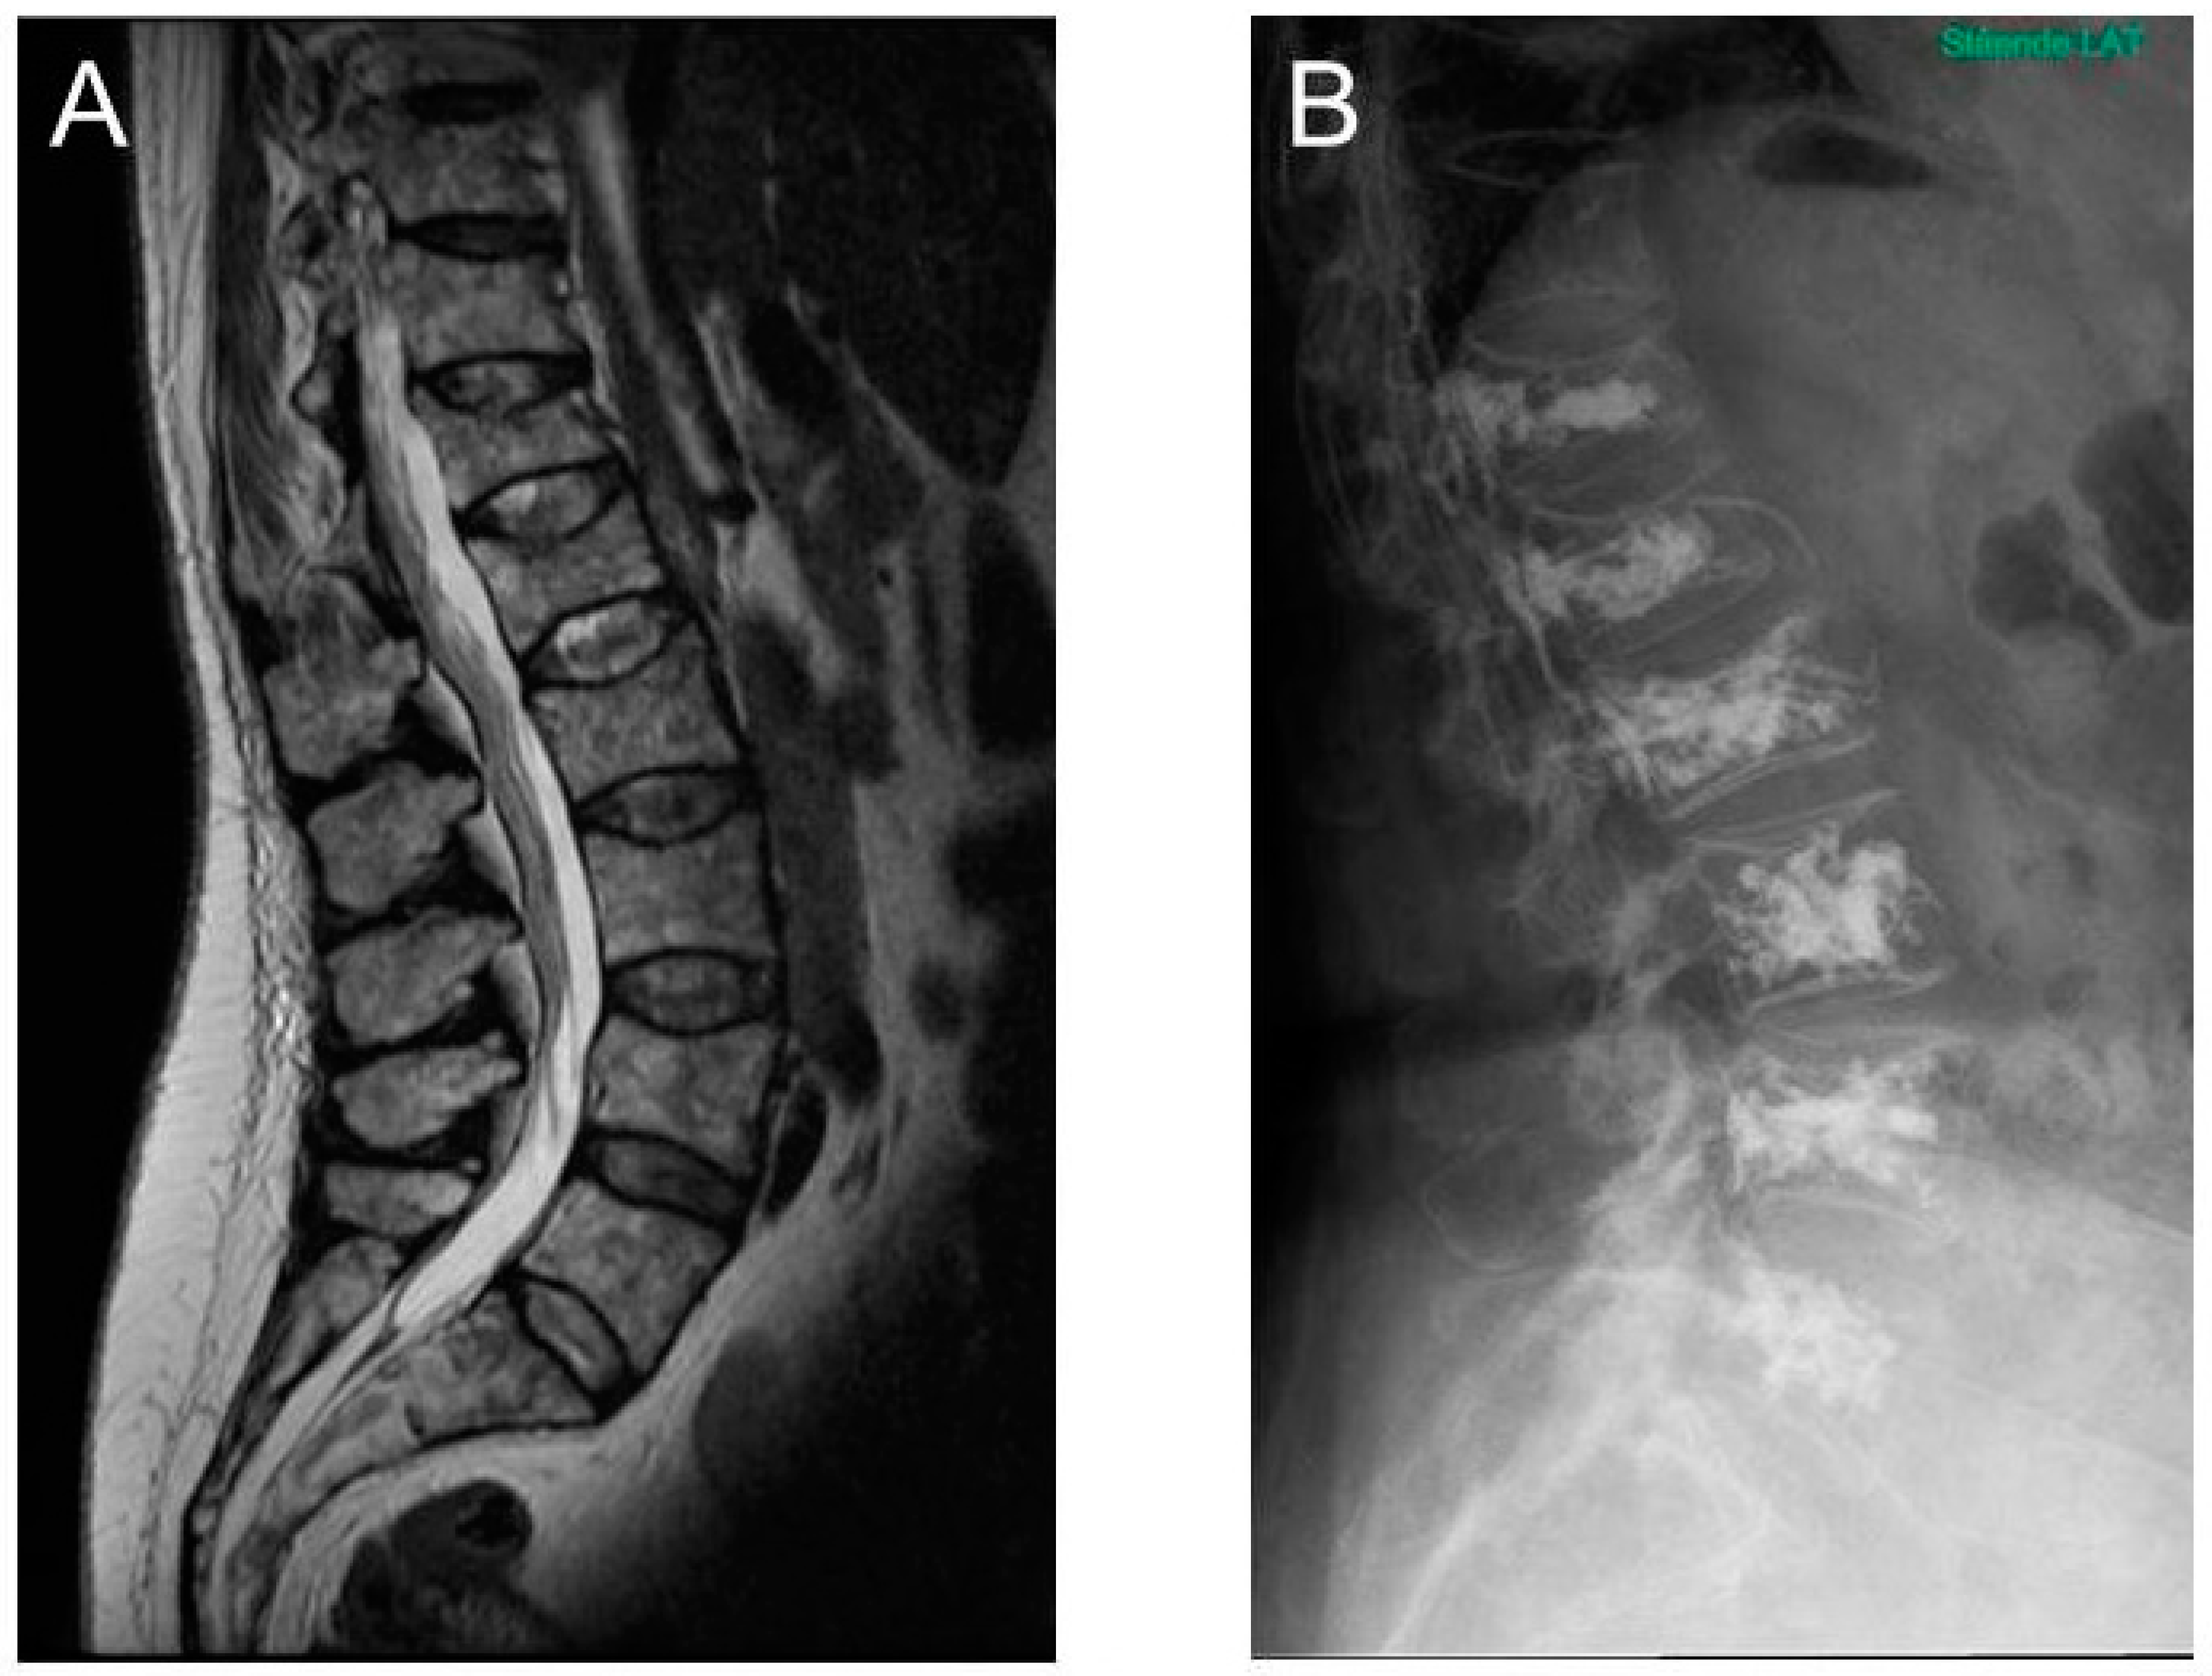

3.3. MRI as a Diagnostic and Prognostic Tool in Patients with Multiple Myeloma

5.2. Vertebral Augmentation